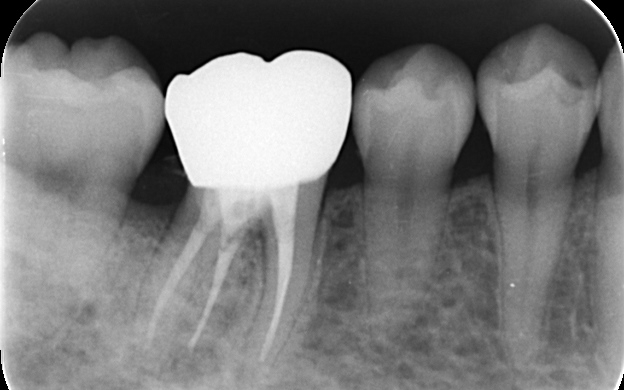

拝見したところ、右下奥歯には歯槽骨(歯を支える骨)の近くまで進行している虫歯が認められました。通常の虫歯治療では、治療が困難な状態です。

まずは歯周外科手術を行い、歯槽骨を必要な分だけ慎重に除去します。その後、健全な歯質が骨の縁から約3mm上に位置するよう精密に調整し、細菌の侵入を長期間防げる状態に整えました。

歯周外科手術を行いました。